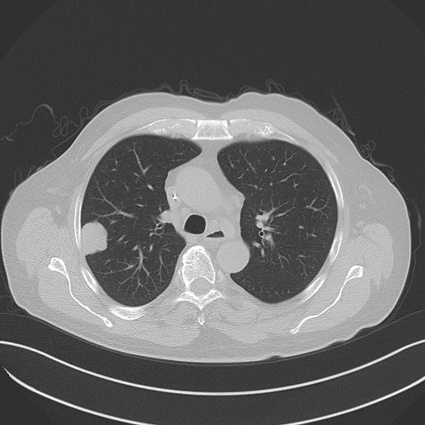

Die Indikationsstellung umfasst derzeit für die percutane Thermoablation mittels Mikrowellenablation Patienten, die nicht mehr resektabel sind, Patienten, die durch die Intervention in eine resektable Situation überführt werden können, die Anzahl der Herde sollte dabei eine Zahl von ≤ 3 nicht überschreiten, die Größe der Herde ≤ 3 max. 4 cm.

Zielsetzung der Mikrowellenablation (und weiteren Ablationstechniken) ist die komplette Destruktion aller vitalen Tumorzellen im Zielvolumen mit einem Sicherheitssaum, Minimierung der Schädigung von Umgebungsstrukturen. Die möglichen Vorteile gegenüber einem chirurgischen Verfahren liegen in der hohen Ortspräzision und dem selektiven Zugangsweg und einer minimal-invasiven Behandlungsstrategie mit tagesstationärer Durchführbarkeit und einer geringeren Belastung des umgebenden normalen Lungenparenchyms. Die Grundlage der Therapie ist dabei die Erzielung einer Temperaturerhöhung intratumoral und in den Sicherheitszonen zwischen 80 und 100 Grad Celsius und geht in der Regel einher mit einer kompletten Destruktion von Zellanteilen wie den Mitrochondrien im Zytoplasma und weiteren Leitstrukturen.

Die besten Daten bezüglich der Ortskontrolle zeigten Lungenmetastasen ≤ 3 cm mit einer möglichst peripheren Lage der Herde.